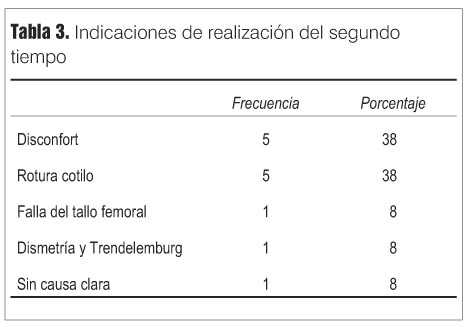

De los 40 casos restantes, 13 pacientes habían requerido el segundo tiempo por diferentes causas que se muestran en la tabla 3, y 27 permanecían con el espaciador al momento del último control.

Del total de pacientes evaluados, 27 casos (67,5%) permanecen con el espaciador y 13 casos (32,5%) requirieron el segundo tiempo por diferentes causas que se muestran en la tabla 3. Todos estos casos habían permanecido con el espaciador por un período de mayor a un año (promedio 29 meses).

Results: the second procedure was needed due to acetabular cement breakage (five cases), discomfort (five cases) and other reasons (three cases). There were two infection relapses, three and five years after surgery.

Resultados: o segundo tempo foi necessário por ruptura de cótilo de cimento (cinco casos), desconforto (cinco casos), y outros motivos (três casos). Nestes pacientes foram registradas duas recidivas de infecção três e cinco anos depois da cirurgia.